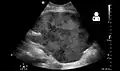

Imaging

Post operatively, kidneys are periodically assessed by ultrasound to assess for the imaging and physiologic changes that accompany transplant rejection. Imaging also allows evaluation of supportive structures such as the anastomosed transplant artery, vein, and ureter, to ensure they are stable in appearance.

The major sonographic scale in quantitative ultrasound assessment is with a multipoint assessment of the resistive index (RI), beginning at the main renal artery and vein and ending at the arcuate vessels. It is calculated as follows:

- RI = (peak systolic velocity – end diastolic velocity ) / peak systolic velocity

The normal value is ≈ 0.60, with 0.70 being the upper limits of normal.[63][64]

- Postoperative bleeding following kidney transplant as seen on ultrasound[79]

Postoperative bleeding following kidney transplant as seen on ultrasound[79]